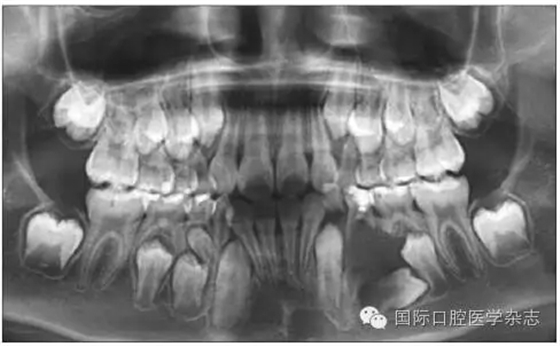

左:口內(nèi)照;右:全景片。

圖7 左上第一恒磨牙異位萌出,左上第二乳磨牙松動(dòng)

Fig 7 Ectopic eruption ofleft upper the first permanent molar, loose of left upper the second primarymolar

牙齒異位萌出是指恒牙在萌出過(guò)程中,未在牙列的正常位置萌出,兒童口腔臨床最常見(jiàn)的是上頜第一恒磨牙和上頜尖牙的異位萌出。造成第一恒磨牙異位萌出的原因包括:第二乳磨牙和第一恒磨牙的牙冠體積較大;頜骨的發(fā)育不足,尤其是上頜結(jié)節(jié)發(fā)育不足;第一恒磨牙的萌出角度異常,牙軸向近中傾斜等,歸根結(jié)底是在第一恒磨牙萌出階段出現(xiàn)了牙量和骨量不調(diào)的問(wèn)題,頜骨發(fā)育不足是最主要的原因。發(fā)生率為2%~6%,男性多于女性,其中2/3發(fā)生在上頜,可單側(cè)或雙側(cè)對(duì)稱(chēng)出現(xiàn)。第一恒磨牙的異位萌出常常造成第二乳磨牙早失,牙弓長(zhǎng)度減小。臨床上,常用分牙簧分離第一恒磨牙與第二乳磨牙,或使用恒磨牙面粘著舌扣的Halterman矯治器,或變異Nance弓推第一恒磨牙向遠(yuǎn)中的方法,改變恒牙萌出道,阻斷恒磨牙對(duì)乳磨牙的壓迫吸收,引導(dǎo)恒磨牙正常萌出。圖7顯示為一左上第一恒磨牙異位萌出的患兒,左上第二乳磨牙松動(dòng),牙弓長(zhǎng)度減少[6]。